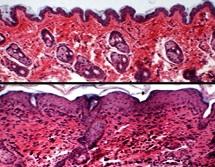

L'eczéma atopique, aussi appelé dermatite atopique, est une dermatose inflammatoire, caractérisée par des périodes de poussées de plaques rouges. L'équipe de dermatologues et cardiologues de la Brown (Providence, US) a analysé les dossiers de 259.119 adultes âgés de 30 à 74 ans participant au programme Canadian Partnership for Tomorrow Project pour vérifier une hypothèse récente : les personnes souffrant de dermatite atopique (DA) seraient beaucoup plus susceptibles de développer des troubles cardiovasculaires. 21.379 participants, soit 8,4% étaient atteints de DA. 52.787 cas d'hypertension artérielle, 12.739 diagnostics de diabète de type 2, 4.390 crises cardiaques et 2.235 AVC ont été signalés par les participants à l'inscription. Les chercheurs ont pris en compte les facteurs de confusion possibles, dont l'âge, le sexe, l'origine ethnique, l'indice de masse corporelle, le tabagisme, la consommation d'alcool, le sommeil, l'activité physique et l'asthme.